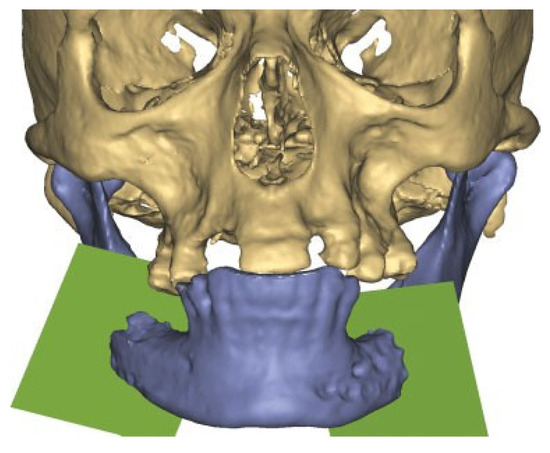

Figure 3.

Patient developed infections with oral mucosal fistulas in the fracture areas and an open bite. CBCT displays obvious anterior rotation of proximal segments and posterior rotation of the dentate part of mandible. Considerable muscle action creates new dislocation and is not counteracted by the inadequate osteosynthesis of the fractures.

Figure 4.

After plate removal in the software, osteotomies in the fracture areas and corrective rotation of displaced fragments was performed to close the open bite and restore the occlusion in the virtual plan.